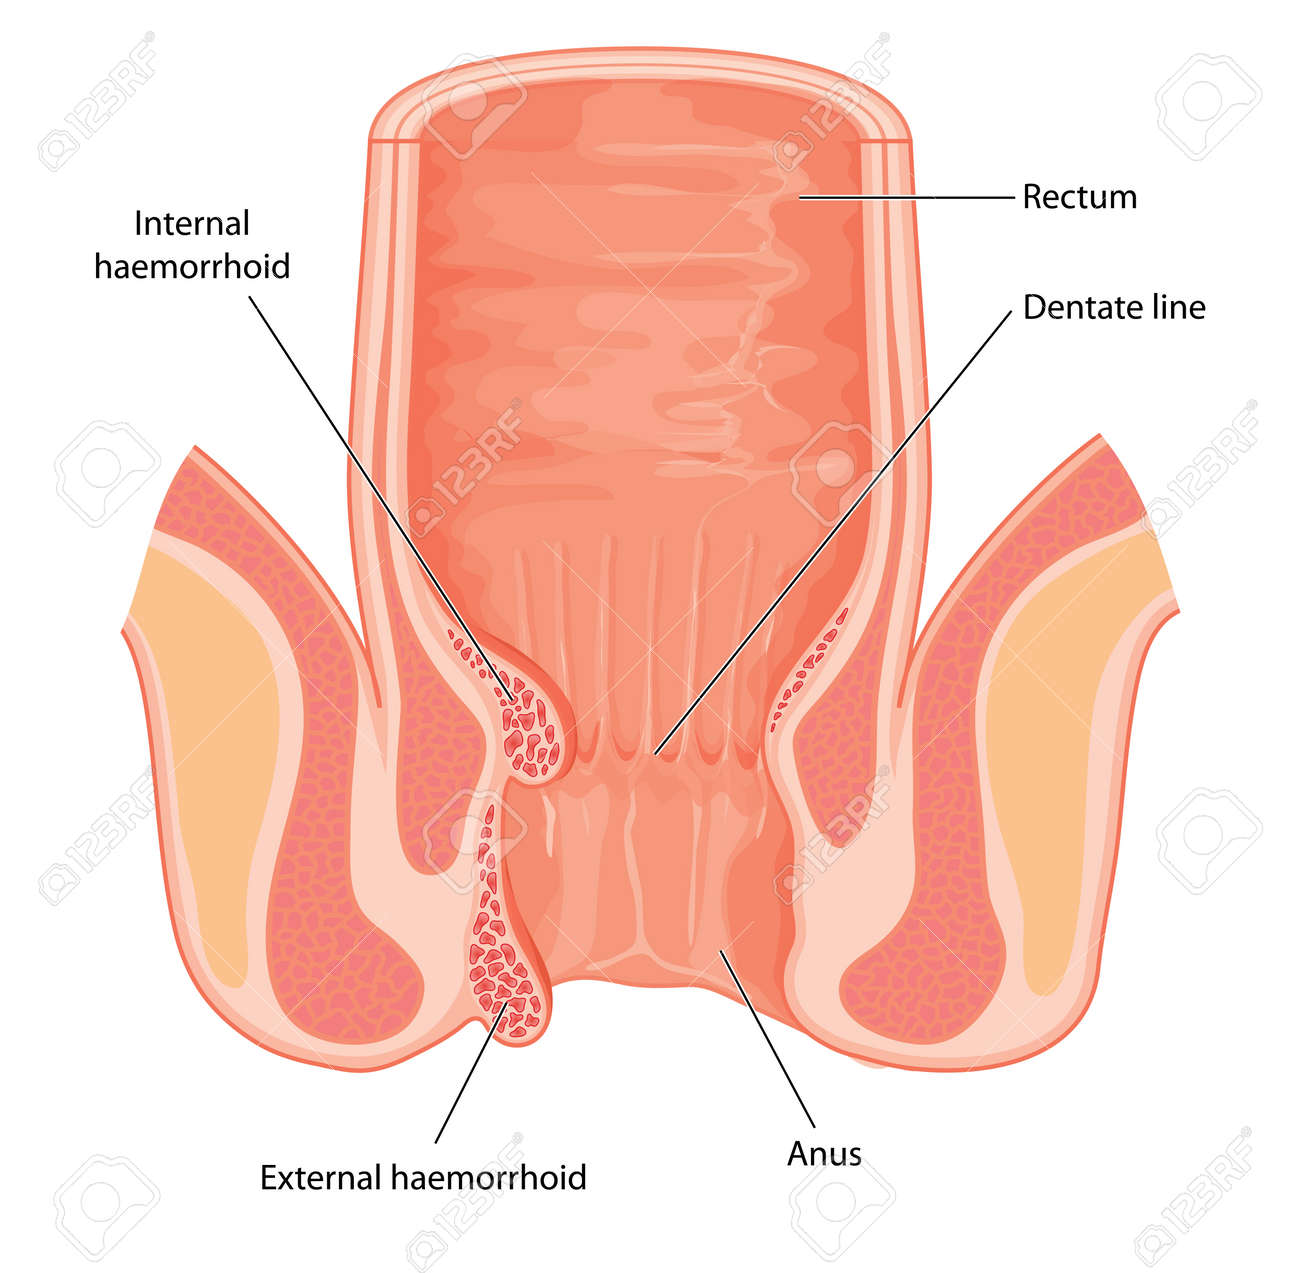

おしりの構造と病気 森外科医院 日本大腸肛門病学会認定施設 日本臨床肛門病学会認定施設 岐阜県大垣市で肛門科をお探しの方は肛門専門病院の森外科医院までご相談下さい

痔について 門田外科医院

痔ってなンだ 4 おしりだって風邪をひく

肛門外科 外科 診療科 部門紹介 外来受診される方 宇治武田病院 武田病院グループ

あなたの痔はどのタイプ 診療方法と肛門科診療のタイミング 内科 整形外科 肛門科 痔 浜中医院 大阪府岸和田市

肛門に多い病気

痔 肛門 断面図 イラスト素材 フォトライブラリー Photolibrary